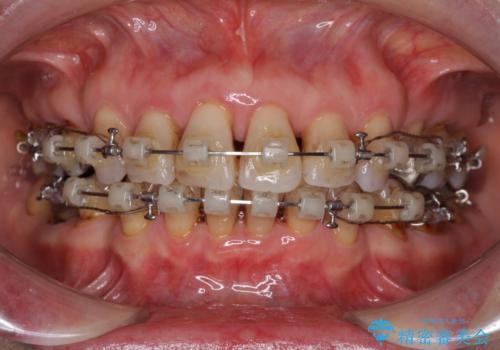

- 矯正装置

- クリアブラケット

- 突出した口元を引っ込めることを希望して来院された患者様です。

上下左右第一小臼歯4本を抜歯して、口元を改善するワイヤー矯正を行うこととしました。